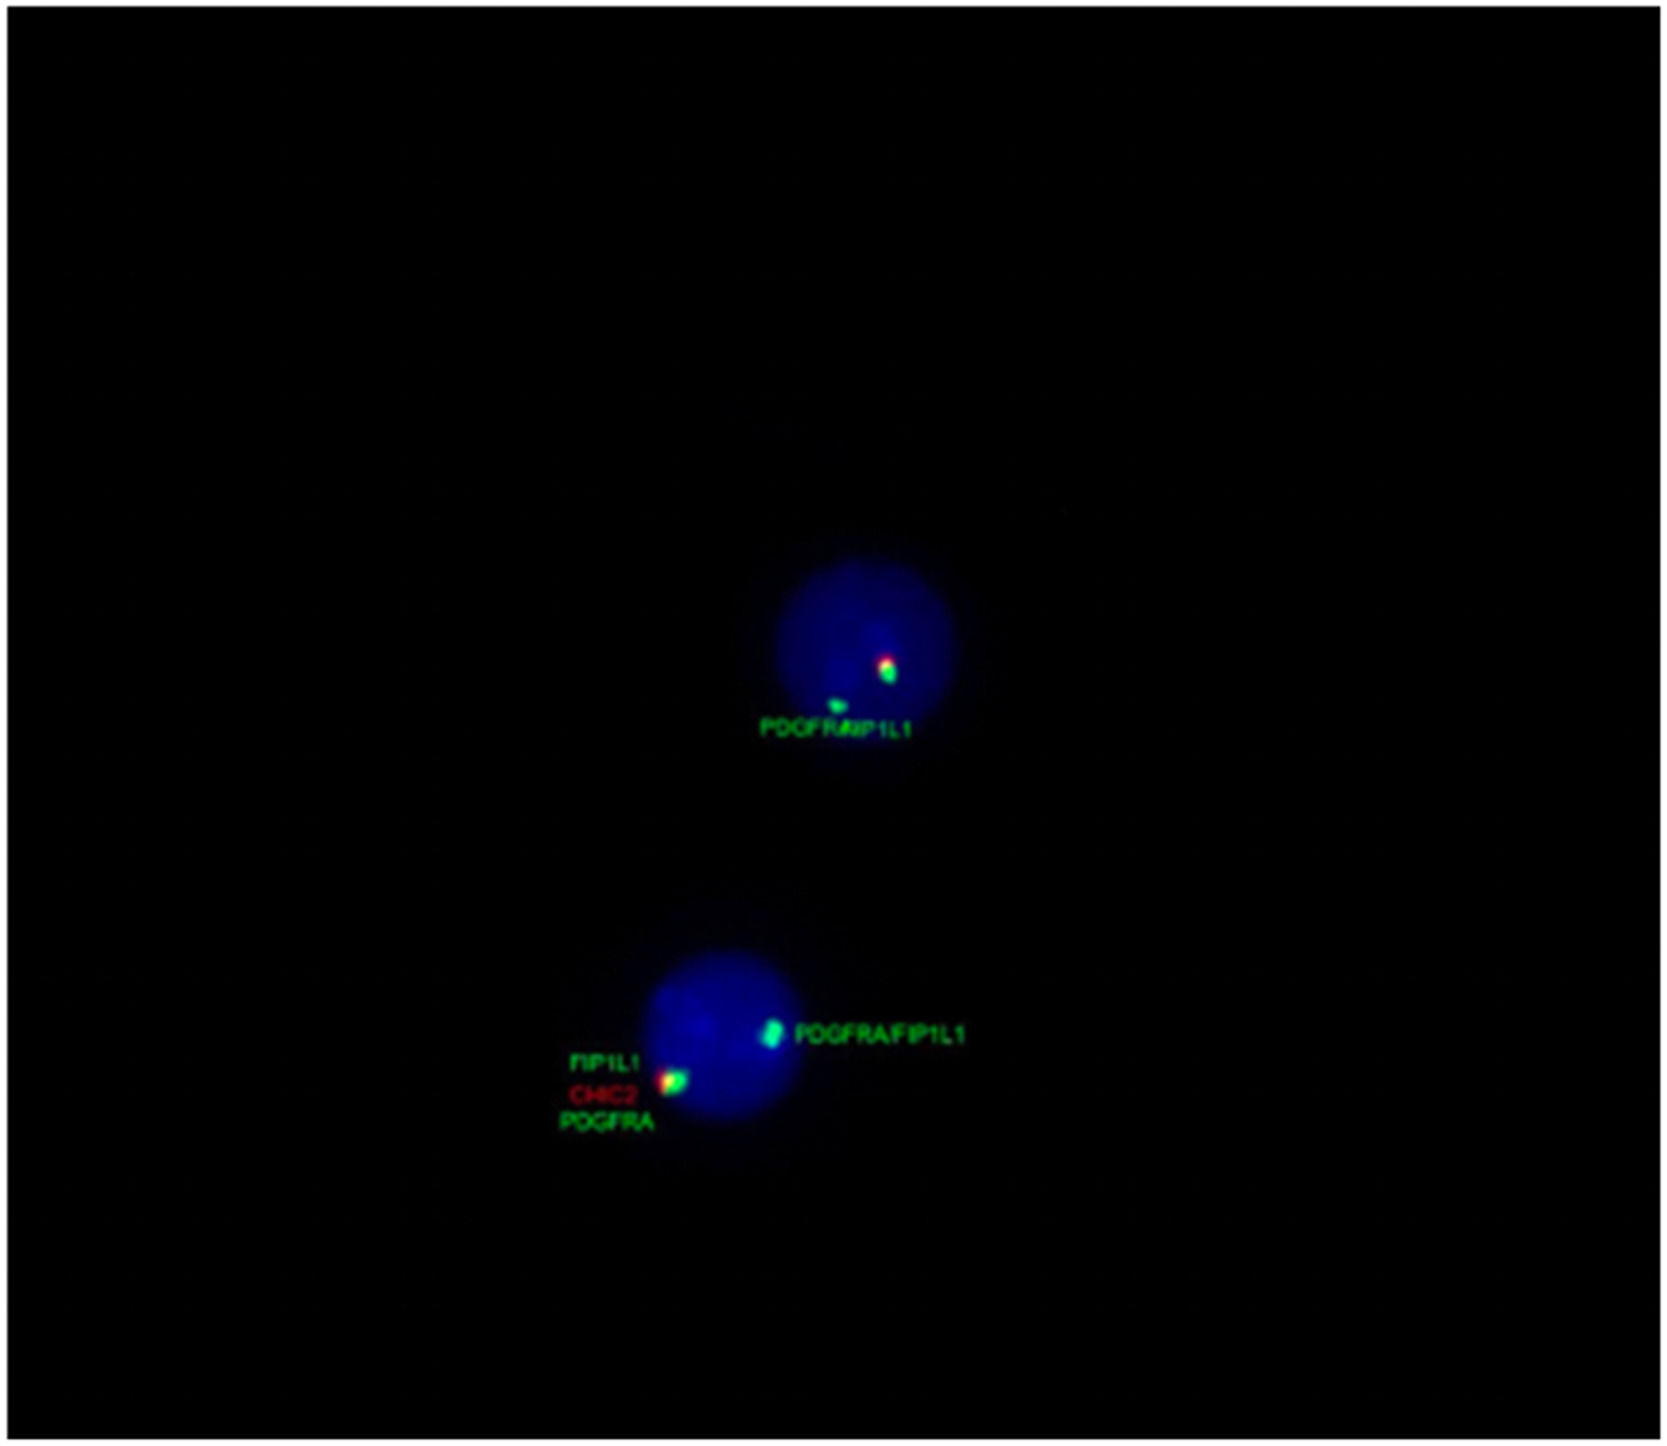

Bone marrow immunophenotyping showed eosinophilia (22 %) with predominance of granulocytic lineage. Tests for BCR::ABL1 and JAK2 were negative, while fluorescence in situ hybridization (FISH) revealed the FIP1L1-PDGFRA rearrangement in 98 % of analyzed nuclei (Figure 2). A biopsy of the right femur confirmed bone infiltration compatible with chronic eosinophilic leukemia.

Diagnosis requires exclusion of secondary causes of eosinophilia, followed by molecular testing for the FIP1L1-PDGFRA fusion gene, an alteration undetectable by standard cytogenetics and requiring techniques such as FISH or reverse transcription polymerase chain reaction (RT-PCR) [1]. In our patient, the rearrangement was detected in 98 % of nuclei by FISH, confirming the diagnosis and guiding targeted therapy.